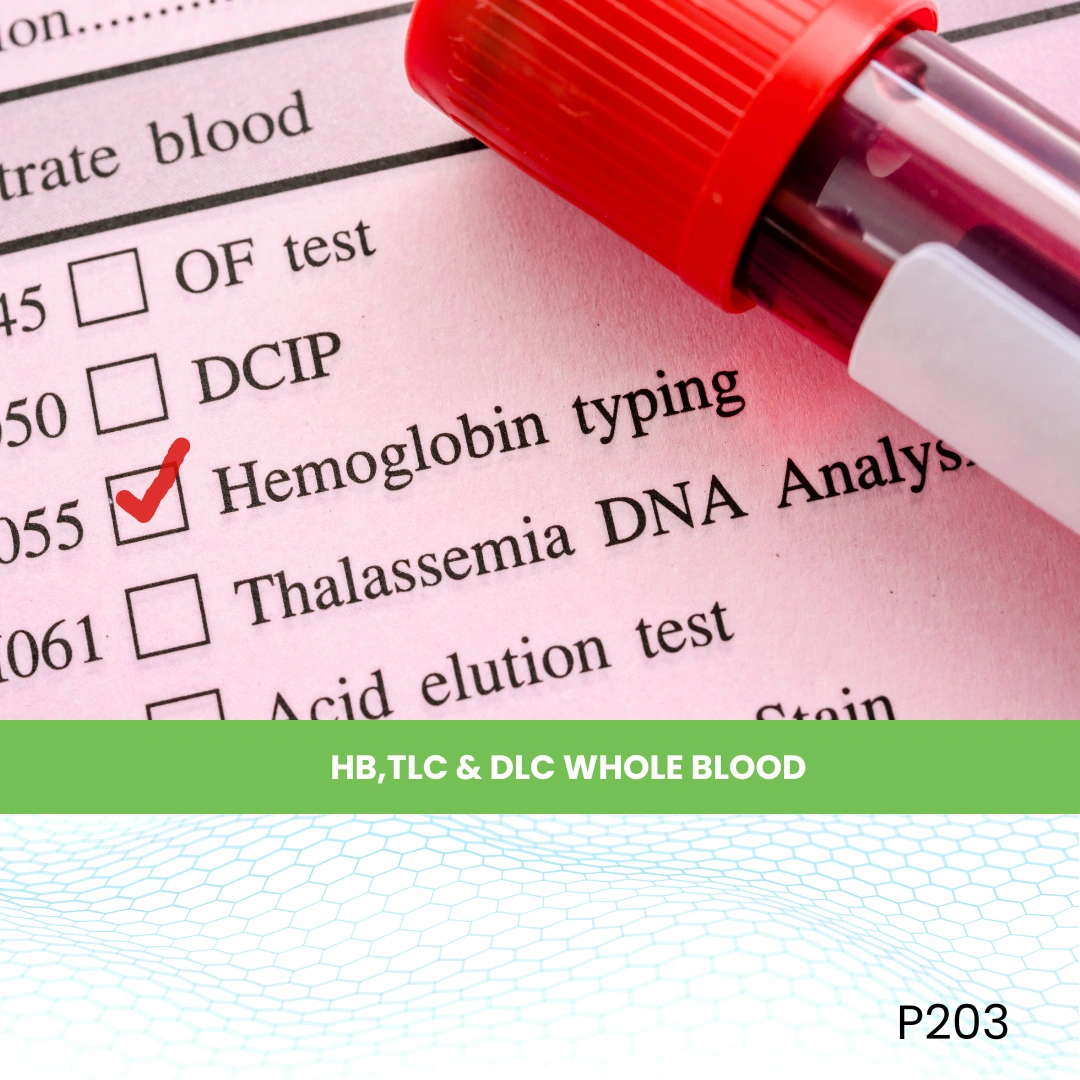

- Blood Test

- Blood Test